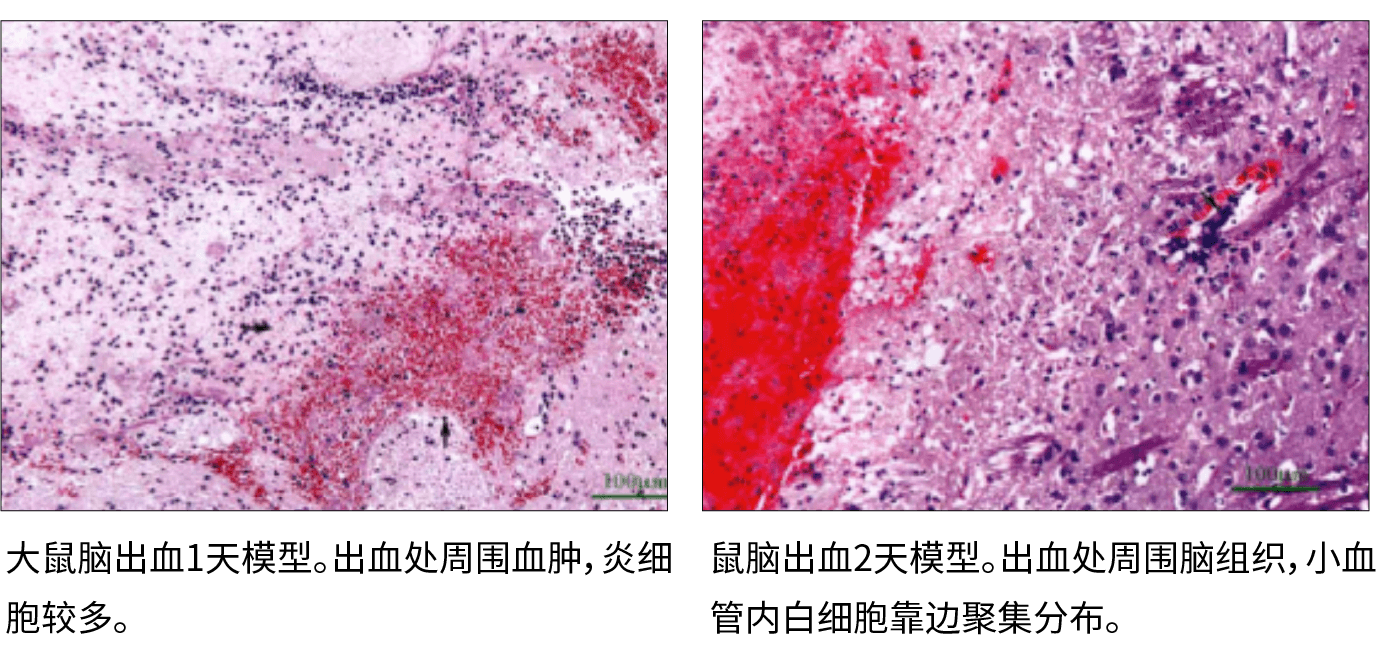

2、脑出血动物模型—病理学特点:出血侧半球肿胀、充血,血液流入蛛网膜下腔或破入脑室,严重者可见脑室移位、变形和脑疝形成。

以下示例为脑出血模型病理改变:

1、HE染色:观察组织基础形态: